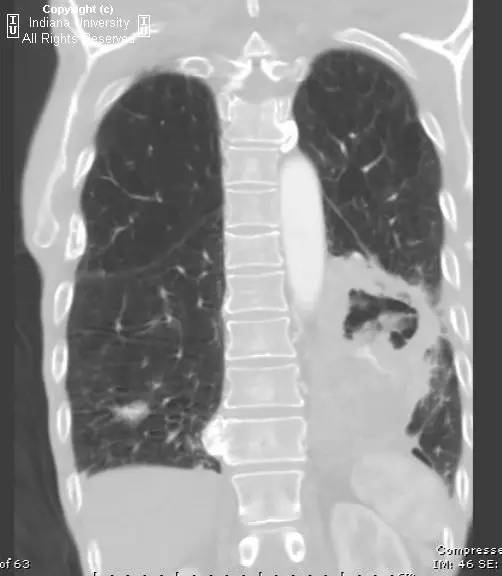

胸片示肺内高度膨胀性病变,膈肌扁平。左后胸部可见较大卵圆形不透亮区并液平面。CT示左肺下叶近后胸壁较大厚壁肿块并部分空洞形成,实性部分不均质强化。右肺下叶可见分叶状结节。左前下少量气胸。

【诊断】鳞状细胞肺癌并后部阻塞性肺炎